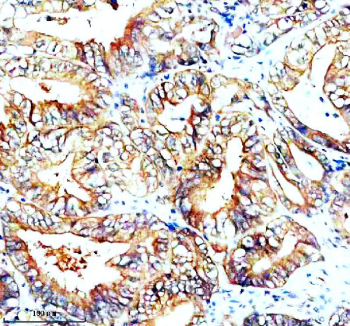

Immunohistochemical staining of SNX2 using anti-SNX2 antibody. SNX2 was detected in a paraffin-embedded section of human thyroid cancer tissue. Heat mediated antigen retrieval was performed in EDTA buffer (pH 8.0, epitope retrieval solution). The tissue section was blocked with 10% goat serum. The tissue section was then incubated with 2 ug/ml rabbit anti-SNX2 antibody overnight at 4oC. Peroxidase Conjugated Goat Anti-rabbit IgG was used as secondary antibody and incubated for 30 minutes at 37oC. The tissue section was developed using an HRP secondary and DAB substrate.